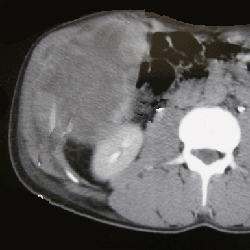

Know Your Hernia: Concurrent Panniculectomy with Complex Abdominal Wall Reconstruction

Dr. Jenny Shao details a case in which concurrent panniculectomy was used to reconstruct a complex abdominal wall during hernia repair.